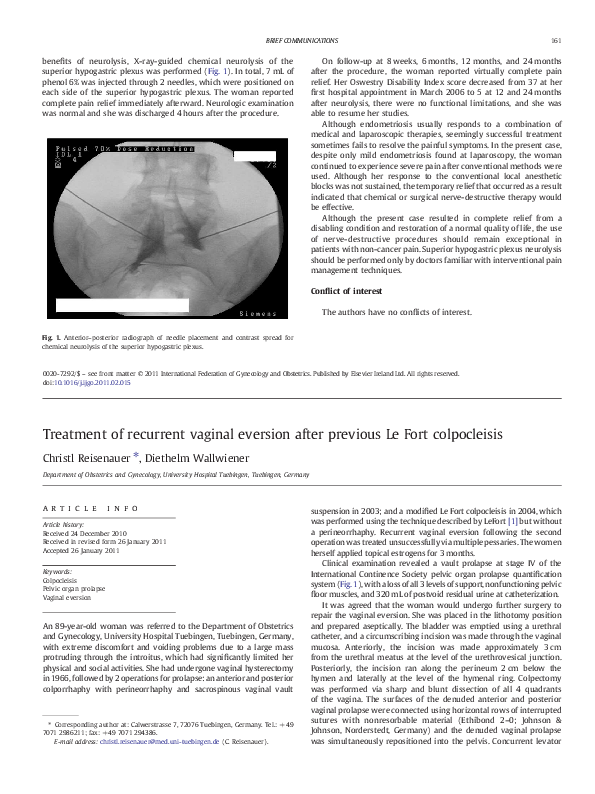

From www.academia.edu

(PDF) Treatment of recurrent vaginal eversion after previous Le Fort Incontinence After Colpocleisis Surgery The incidence of de novo urinary incontinence after colpocleisis was very low. This was a longitudinal study of patients who underwent colpocleisis at least 2 years previously. Unmasking of stress incontinence of urine that was hidden by the kink of the urethra, associated with prolapse. Although it is difficult to predict de novo urinary incontinence after surgery, preoperative screening of. Incontinence After Colpocleisis Surgery.